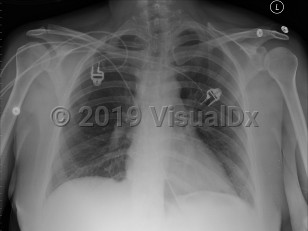

Pulmonary embolism

A PE is a blood clot that typically originates from thrombi in the deep venous system of the legs and travels to the lungs. It can also originate from deep pelvic veins, rectal veins, the inferior vena cava, the right heart, and the axillary veins. Approximately 10% of cases are fatal.

The clinical presentation depends upon the size, location, number and chronicity of emboli, and the patient's cardiorespiratory reserve. Often symptoms are nonspecific. Features may include dyspnea and tachypnea, chest pain (most commonly pleuritic), cough, tachycardia, arrhythmia, palpitations, hemoptysis, thigh and/or leg pain and/or swelling, pleural effusion, pulmonary infiltrates, cyanosis, syncope, and, in some cases, sudden death (classically pulseless electrical activity [PEA] arrest).